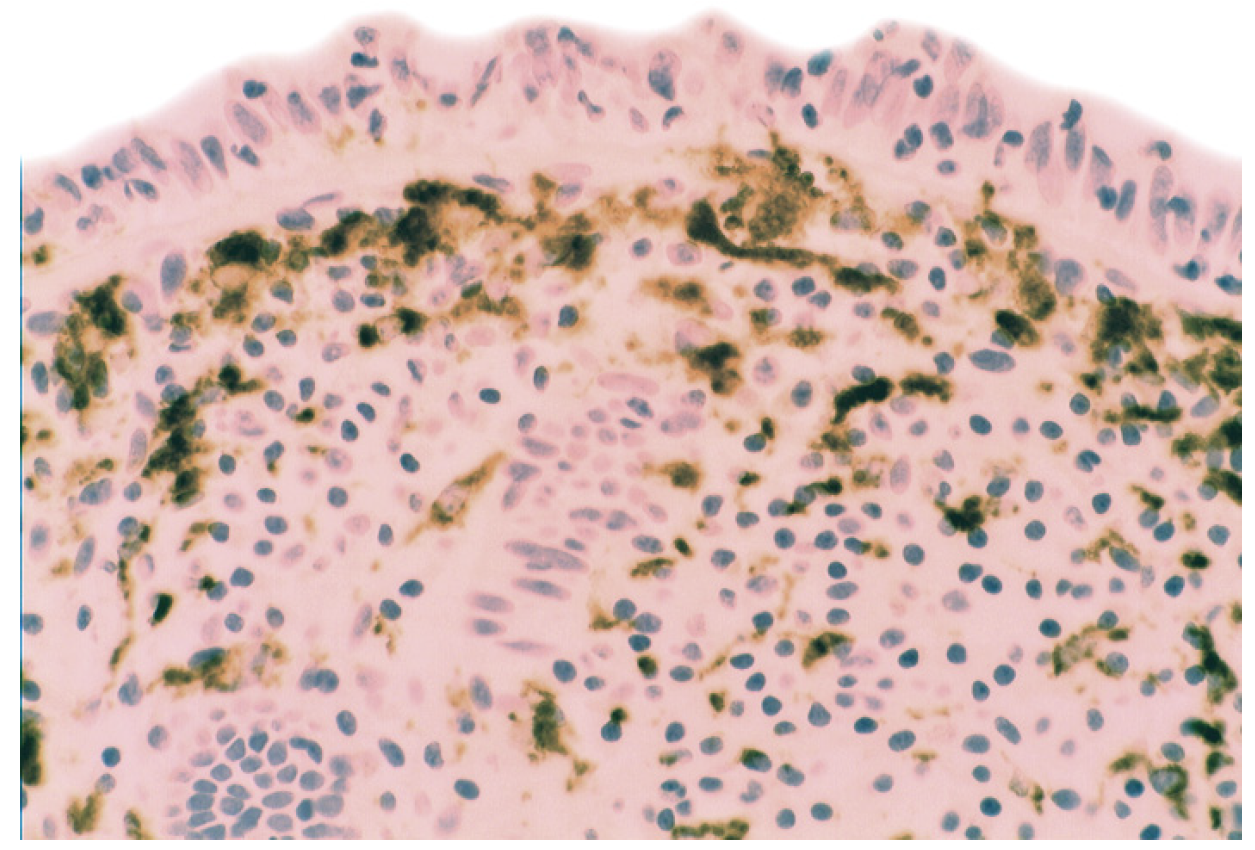

In collagenous colitis lysozyme is up-regulated in the colonic crypts and in metaplastic Paneth cells [9] (Figure 11). In lymphocytic colitis, lysozyme is up-regulated in macrophages underlying the surface epithelium of the lamina propria [9] (Figure 12), as well as in the lower part of the crypts (Figure 13).

Figure 12.

Lymphocytic colitis showing marked lysozyme expression, in macrophages in the lamina propria juxtaposing the superficial epithelium (lysozyme immunostain, ×40).